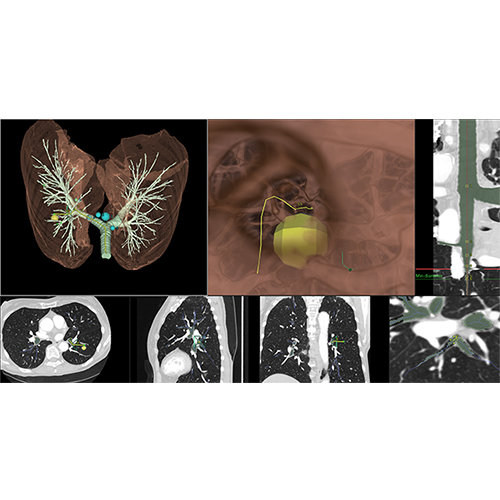

了解更多